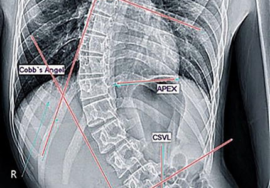

الأشعة السينية: لتحديد زاوية الانحناء بدقة (زاوية كوب).